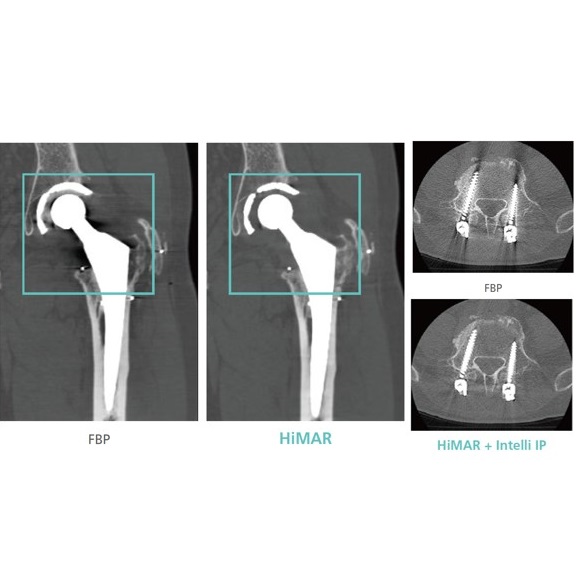

- HiMAR - technika redukcji artefaktów wywołany przez metalowe implanty

- Intelli IP Advance - technologia redukcji szumów z rekonstrukcją iteracyjną dla niskiej dawki i wysokiej jakości obrazu